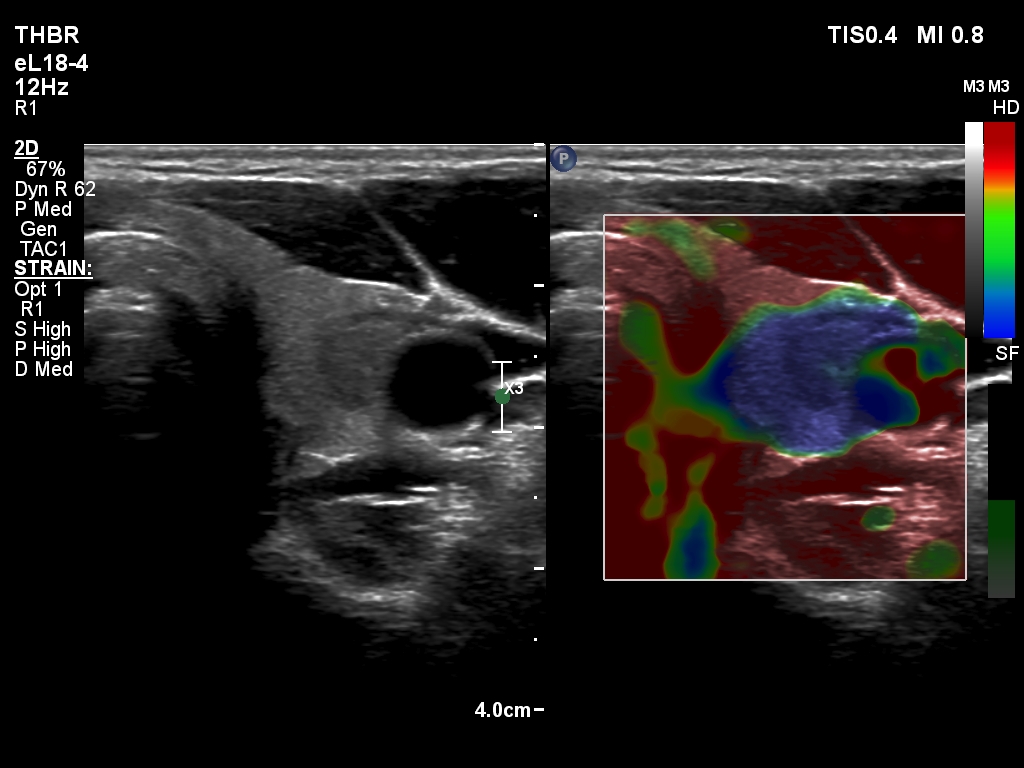

Left lobe, transverse scan, elastography. The nodule proved to be soft.